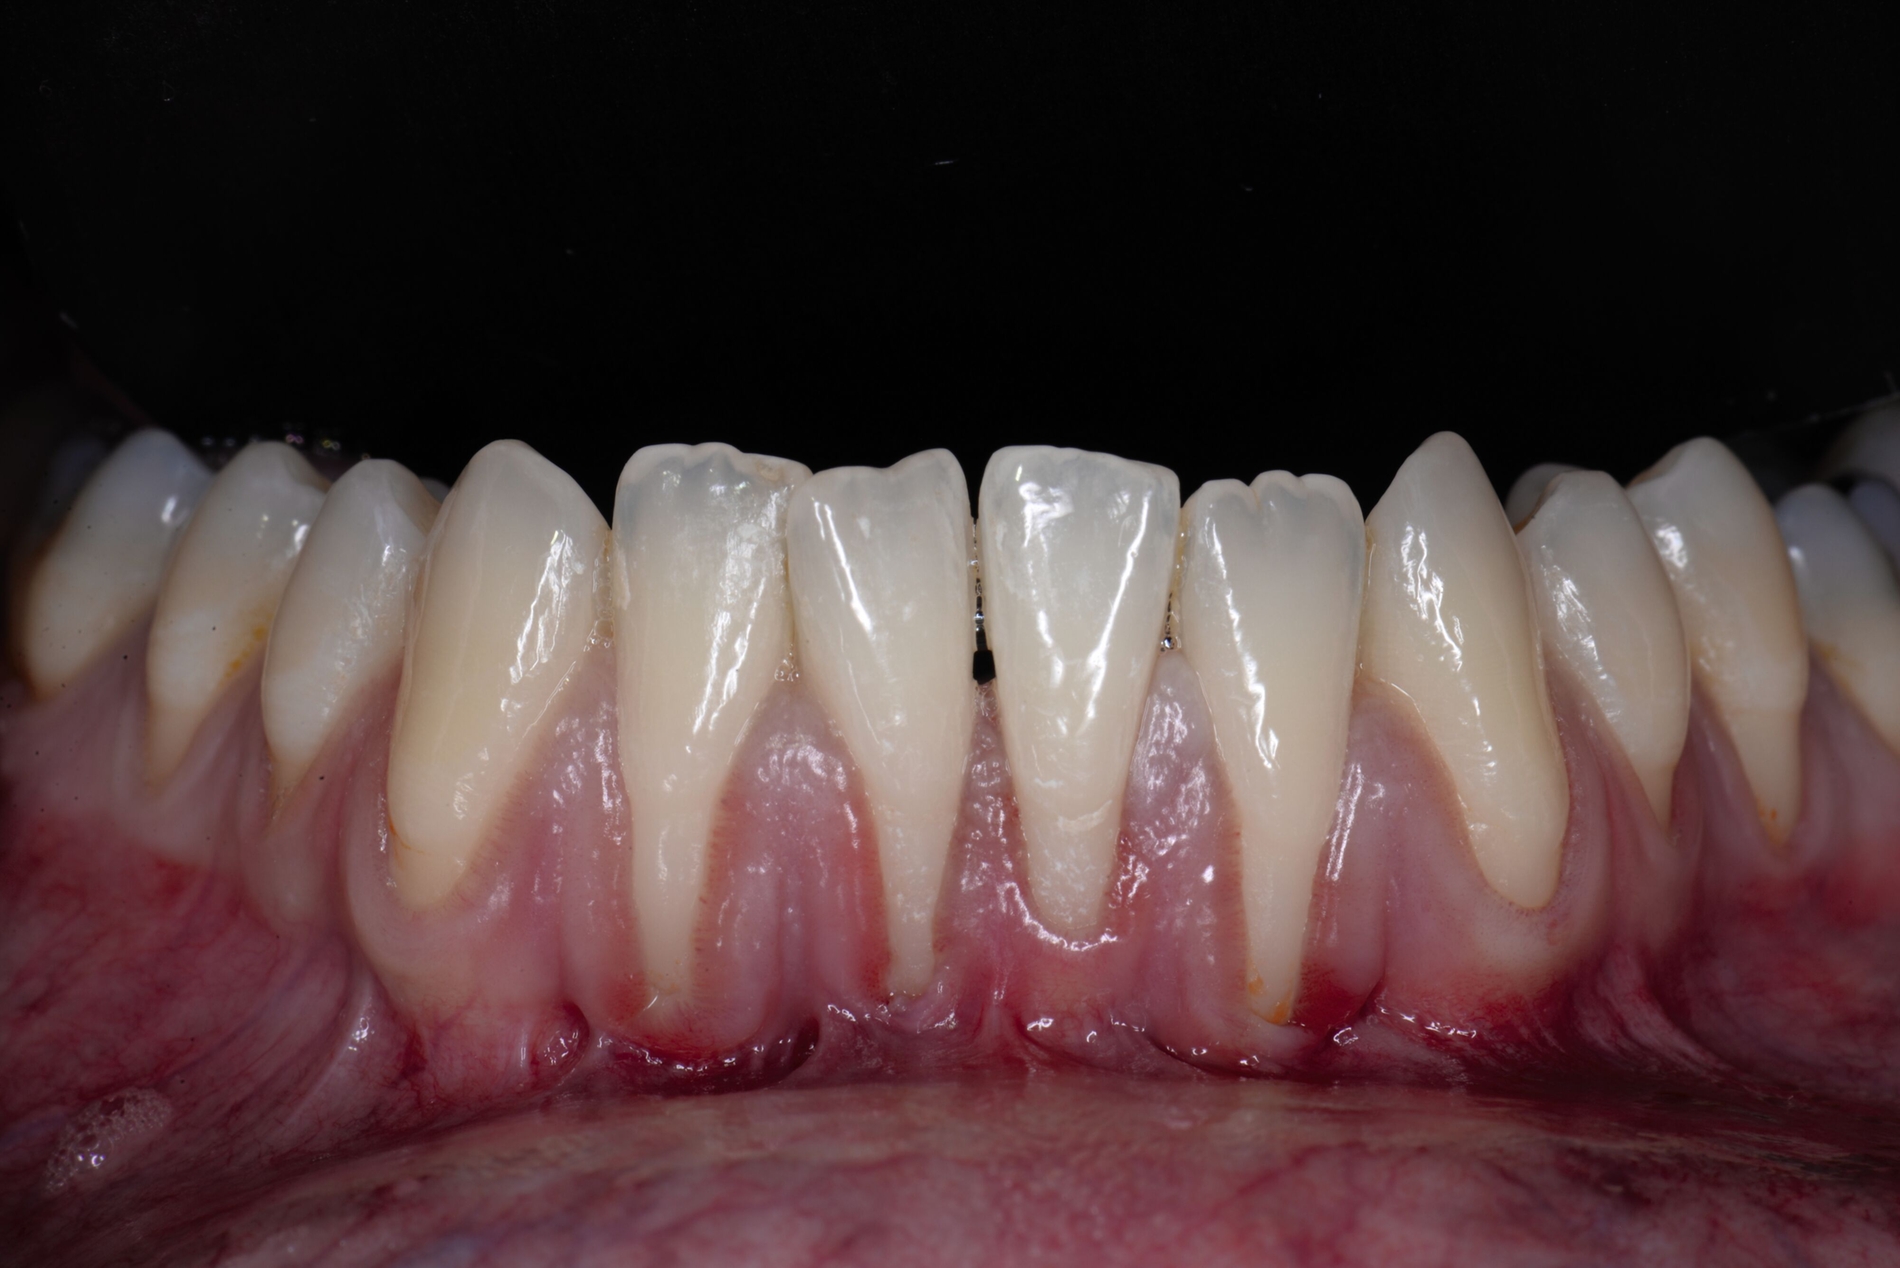

Tunkel et al. versuchten die Vorteile von Zucchellis Koronalem Verschiebelappen und Sculeans Lateral Geschlossenem Tunnel in einer Technik zu vereinen: dem Lateral Geschlossenen Koronalen Verschiebelappen (LCAF) [Tunkel et al., 2024] (Abbildung 3). Bei dieser Methode, mit der vor allem tiefe singuläre parodontale Rezessionen behandelt werden, wird die Koronalverschiebung ohne Entlastungsinzisionen kombiniert mit dem lateralen Verschluss der tiefen parodontalen Rezession.

Das Vorgehen ist hier wie folgt: Zunächst wird im Bereich der tiefen Rezession der Gingivarand geringfügig exzidiert, um ein Zusammenwachsen der geschlossenen Lappenanteile zu ermöglichen. Anschließend wird der Schnitt in horizontaler Richtung durch leicht bogenförmige Schnittführungen auf Höhe der Schmelz-Zement-Grenze erweitert, um mindestens zwei Zähne rechts und links von der Rezession (Abbildung 3b). Im Unterkiefer-Frontzahnbereich, wo die Rezessionen heutzutage am häufigsten vorkommen, sollte der Lappen mindestens von Eckzahn zu Eckzahn gebildet werden, um ein harmonisches Ergebnis nach Abheilung zu erreichen. Auf vertikale Entlastungsinzisionen kann komplett verzichtet werden. Anschließend erfolgt die Lappenpräparation nach dem bereits für koronale Verschiebelappen gängigen Prinzip teilschichtig-vollschichtig-teilschichtig.

Die Papillenbereiche werden mit dem Skalpell scharf vom Periost abgelöst. Dann wird das Periost durchtrennt und bis zur mukogingivalen Grenze ein vollschichtiger Lappen gebildet. Nach Überschreiten dieser wird wieder zweischichtig präpariert. Hierdurch wird eine gute Mobilisation des Lappens erreicht, die eine ausreichende Koronalverschiebung ermöglicht. Entgegen dem in früheren Jahren propagierten komplett teilschichtigen Vorgehen, kann durch dieses Verfahren die Gefahr von Lappenperforationen signifikant gesenkt werden, da diese insbesondere im Bereich der mukogingivalen Grenze auftreten. Nachdem die Lappenareale mesial und distal der Rezession gelöst sind, können diese durch zwei bis drei feine monofile Nähte miteinander verbunden werden (Abbildung 3c). Sobald durch diese Naht ein zusammenhängender koronaler Verschiebelappen entstanden ist, werden die Papillenbereiche koronal des gebildeten Lappens entepithelialisiert. Nach Entnahme eines Bindegewebstransplantats oder entepithelialisierten freien Schleimhauttransplantats wird die Wurzeloberfläche mit EDTA-Gel konditioniert und anschließend werden Schmelz-Matrix-Proteine aufgetragen (Abbildung 3d). Diese bewirken die Bildung eines new attachment und fördern zudem die Wundheilung, was gerade bei den delikaten lateralen Verschiebelappen von Vorteil sein sollte [McGuire und Cochran, 2003; Almqvist et al., 2011; Thoma et al., 2011; McGuire et al., 2016]. Anschließend wird das Transplantat durch Nähte ausgehend vom oralen Papillenbereich fixiert (Abbildung 3e). Zuletzt wird der Lappen mit sogenannten doppelten Umschlingungsnähten im Bereich der Papille durch Zug nach koronal und oral fixiert, was eine perfekte Positionierung ermöglicht [Zuhr et al., 2009] (Abbildung 3f). Hierbei muss darauf geachtet werden, dass der Lappen die Schmelz-Zement-Grenze um mindestens 2 mm überdeckt, um eine hundertprozentige Wurzeldeckung erwartbar zu machen [Pini Prato et al., 2005].

Der Lateral Geschlossene Koronal Verschobene Lappen ermöglicht eine annähernd narbenfreie Deckung singulärer parodontaler Rezessionen durch Verzicht auf vertikale Entlastungsinzisionen (Abbildung 3g). Das Lösen der Papillen im Rahmen der Verschiebung ermöglicht eine deutliche Anhebung des Lappens und somit durch großzügige Überdeckung das Erreichen vollständiger Wurzeldeckungen. Durch den lateralen Verschluss im Rahmen der tiefen, über die mukogingivale Grenze hinausgehenden Rezession kann keratinisierte Gingiva im Bereich dieser hergestellt und eine übermäßige Mobilisation und damit Einschränkung des Vestibulums verhindert werden.